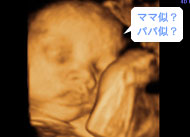

目も鼻も口もはっきりわかります。頬もふっくらしてきたみたい。(妊娠34週)